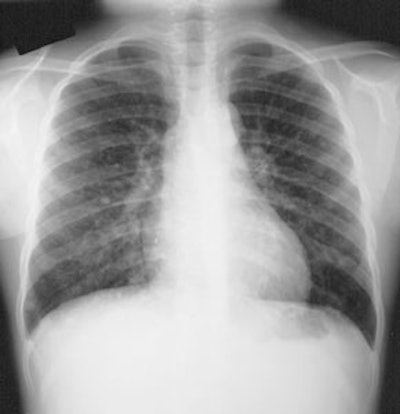

The most common site for distant metastatic disease is the lung [22]. Overall, men have a higher incidence of pulmonary mets. Between 50-60% of metastatic pulmonary lesions will concentrate radioiodine [6]. Patients with iodine concentrating pulmonary metastases have a 5-year survival rate of 60% compared to 30% for tumors which do not concentrate radioiodine [13]. The early (pre-radiographic) scintigraphic diagnosis and I-131 therapy of lung mets appears to be the most important element in obtaining both a significant improvement in survival rate and a prolonged disease free time interval in these patients. In patients with a negative CXR, but positive I-131 scans, there was a 10 year survival rate of 96% and a complete disease remission rate of 80% following I-131 therapy. In patients with both a positive CXR and a positive I-131 scan, the 10 year survival rate was significantly lower (40%) and complete remission was rarely achieved (4%). Patients with a positive CXR, but a negative I-131 scan had the worst prognosis with a 10 year survival rate of only 10% and no complete remissions. In summary- the presence of iodine concentrating pulmonary mets with a negative CXR appears not to influence mortality, however, non-concentrating micro- or macronodular mets do increase mortality risk.

Pulmonary metastases may appear on CT as micronodules (less than 5 mm), macronodules, or the lesions may be radiographically occult and only identified following I-131 imaging or treatment [22]. The micronodular pattern (miliary) of lung mets is invariably related to good I-131 uptake and a better prognosis, while macronodular (over 0.5 cm) mets frequently showed poor uptake and had an associated worse prognosis (fatal outcome was almost always observed in patients with macronodular mets and no I-131 accumulation). Reported 5 year survival rates are 100% for CT occult disease, 88% for micronodules, and 25% for macronodules [22].

Diffuse lung metastases: The patient was an 8 year old female with thyroid cancer. The I-131 exam demonstrated diffuse pulmonary tracer accumulation consistent with metastatic disease. The CXR demonstrated multiple small pulmonary nodules (Click CXR to enlarge image) |